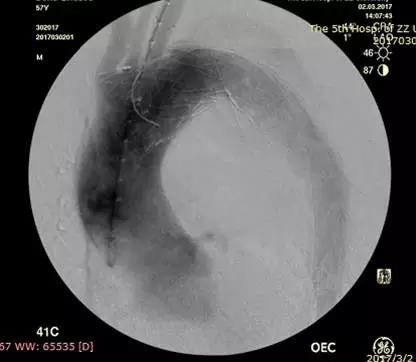

植入分支支架,左锁骨下动脉通畅,无明显内漏

手术设计巧妙,过程顺利,王兵教授主刀,崔文军副主任等医师密切配合,整个手术过程仅耗时2小时。复查造影显示主动脉支架位置良好,破口封堵满意,无内漏,左锁骨下动脉支架通畅,无脑梗塞、肢体及内脏缺血等并发症的发生。整个手术过程中,胡强夫教授带领麻醉团队严格控制血压、心率水平,为手术保驾护航,术后在施敏护士长带领的护理团队精心的护理下,患者恢复良好。